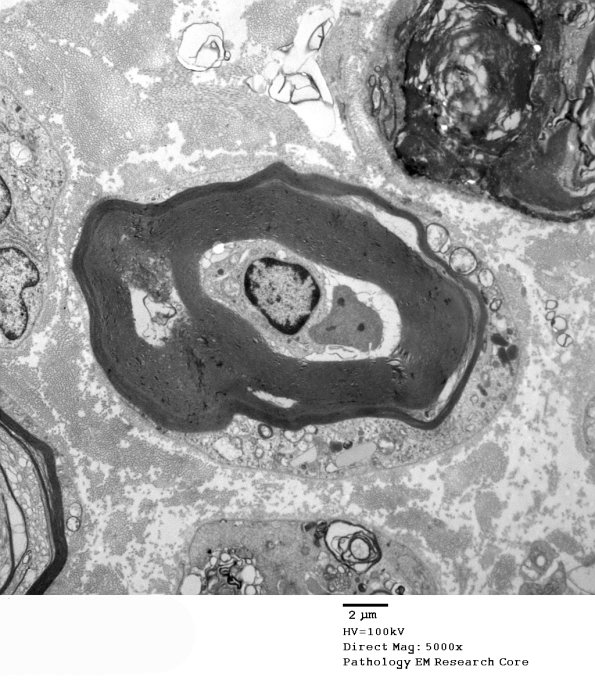

2B2,3 Higher magnifications of image #2B1. (electron micrographs)